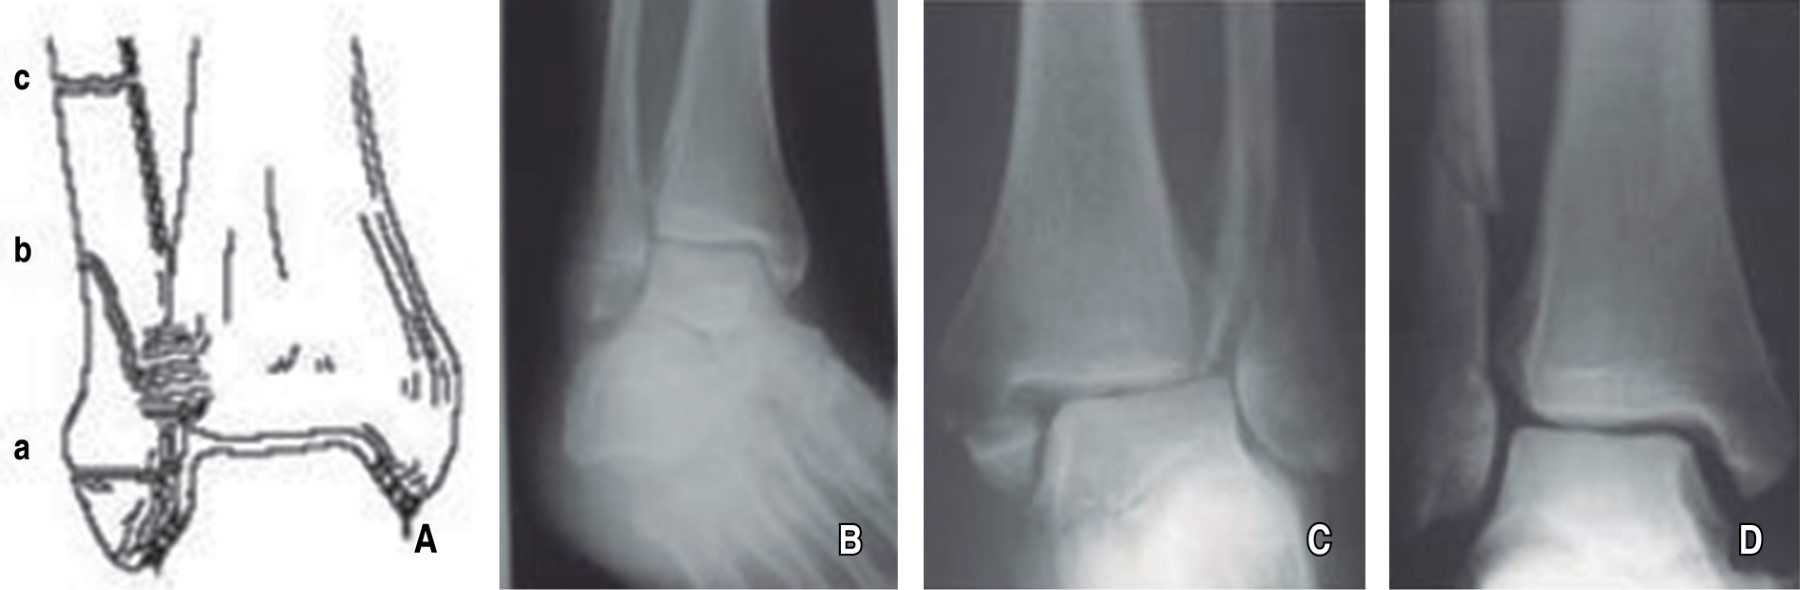

Isolated medial malleolus fracture Mtwortho Medial Malleolus Fracture Walking Boot Do not place ice in. Apply ice packs or a bag of frozen peas wrapped in a wet thin towel to your injured area for up to 15 minutes every few hours. In rare cases, if the bone fragment and main bone are too far apart to fuse naturally, surgery may be needed to reunite them. Avulsed bone fragments can. Medial Malleolus Fracture Walking Boot.

5 Kinds of Medial Malleolus Ankle Fractures Medial Malleolus Fracture Walking Boot If you are unable to bear weight and. In rare cases, if the bone fragment and main bone are too far apart to fuse naturally, surgery may be needed to reunite them. Fractures of the ankle joint are common amongst adults. This often causes the patient to limp so as to protect the medial malleolus. Avulsed bone fragments can be. Medial Malleolus Fracture Walking Boot.

Treatment Of Medial Malleolus Fracture OrthoFixar 2024 Medial Malleolus Fracture Walking Boot In rare cases, if the bone fragment and main bone are too far apart to fuse naturally, surgery may be needed to reunite them. Patients with a medial malleolus fracture typically experience a sudden onset of sharp, intense inner ankle or lower leg pain at the time of injury. Do not place ice in. Avulsed bone fragments can be put. Medial Malleolus Fracture Walking Boot.

A and B show the “horizontal” fracture line of the lateral malleolus Medial Malleolus Fracture Walking Boot Apply ice packs or a bag of frozen peas wrapped in a wet thin towel to your injured area for up to 15 minutes every few hours. If you are unable to bear weight and. Patients with a medial malleolus fracture typically experience a sudden onset of sharp, intense inner ankle or lower leg pain at the time of injury.. Medial Malleolus Fracture Walking Boot.